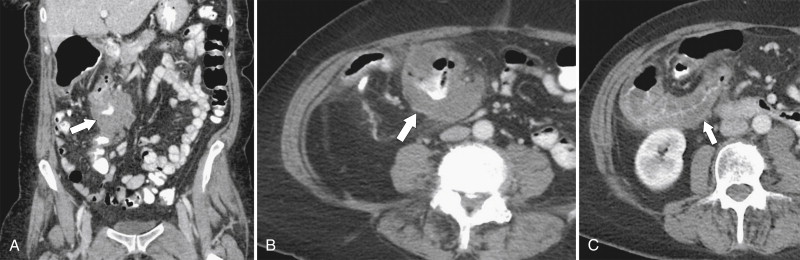

Plain radiography may demonstrate an ileus, sometimes confined to the left colon. As the disease progresses, bowel wall thickening develops ( Fig. 5-34 ) with a toxic megacolon if severe ( Fig. 5-35 ). BE is now rarely performed, but results demonstrate thickened folds and ulceration, either linear or with mucosal sloughing. Healing can lead to stricture formation ( Fig. 5-36 ). The findings are now usually made by CT and are similar to other forms of colitis (inflammatory bowel disease, infectious colitides, and radiation colitis if the radiation field included the colon). The disease is suggested in the appropriate clinical setting and by the left-sided distribution of the colonic changes ( Fig. 5-37 ). Severely affected patients show colonic pneumatosis as the gas permeates the damaged mucosa, which can then enter the mesenteric venous system and be recognized as mesenteric venous gas (particularly at CT) and ultimately intrahepatic portal venous gas. Occasionally, ischemia occurs proximal to an obstructing colonic stricture, such as colonic adenocarcinoma. The obstruction causes marked distention of the proximal colon, compromising its vascular supply or directly invading mesenteric vasculature ( Fig. 5-38 ).

Figure 5-38, A through C, Coronal and axial contrast-enhanced CT in a 62-year-old man with a transverse colon adenocarcinoma ( arrows ) with proximal ascending colon mucosal thickening due to secondary ischemia.